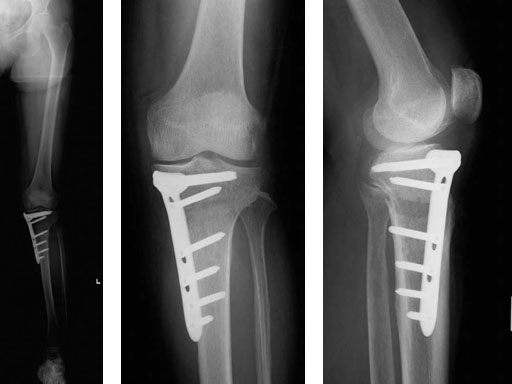

65-year-old female. Osteoarthritic patient complaining of medial knee pain of her left knee.

Case provided by Takeshi Sawaguchi, Toyama, JP

Follow-up in this case is short, because the TomoFix small only became available in August 2008.